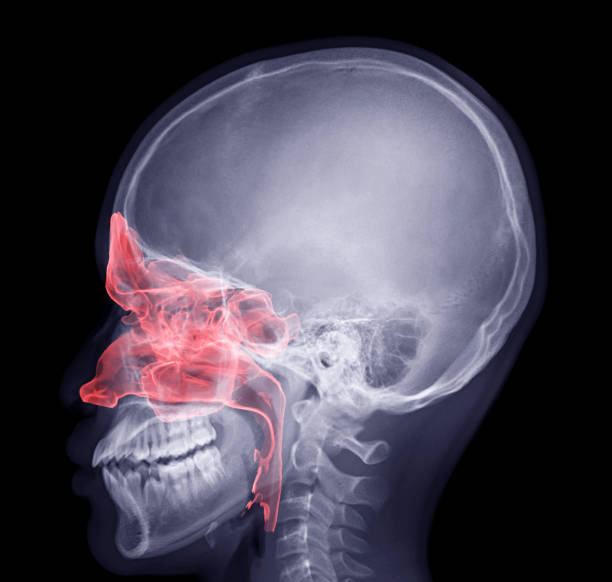

비강암은 코안의 빈 공간인 ‘비강’에 발생하는 암으로

상대적으로 드문 암이나, 조기 발견이 어렵고 비강 주변에 뇌, 눈, 구강 등 중요한 구조물이 밀집해 있어

비강암의 발생 위치에 따라 치료에 어려움이 있을 수 있고, 예후도 차이가 나는 암입니다.

비강암(nasal cavity cancer)은 이름 그대로, 코안의 빈 공간인 비강에 발생하는 악성 종양입니다.

비강암과 함께 자주 언급되는 부비동암(paranasal sinus cancer)은 비강 주위의 동굴 같은 공간인 부비동에 발생하는 암인데, 부비동암을 포함하여 '비강암'이라고 지칭하기도 합니다.